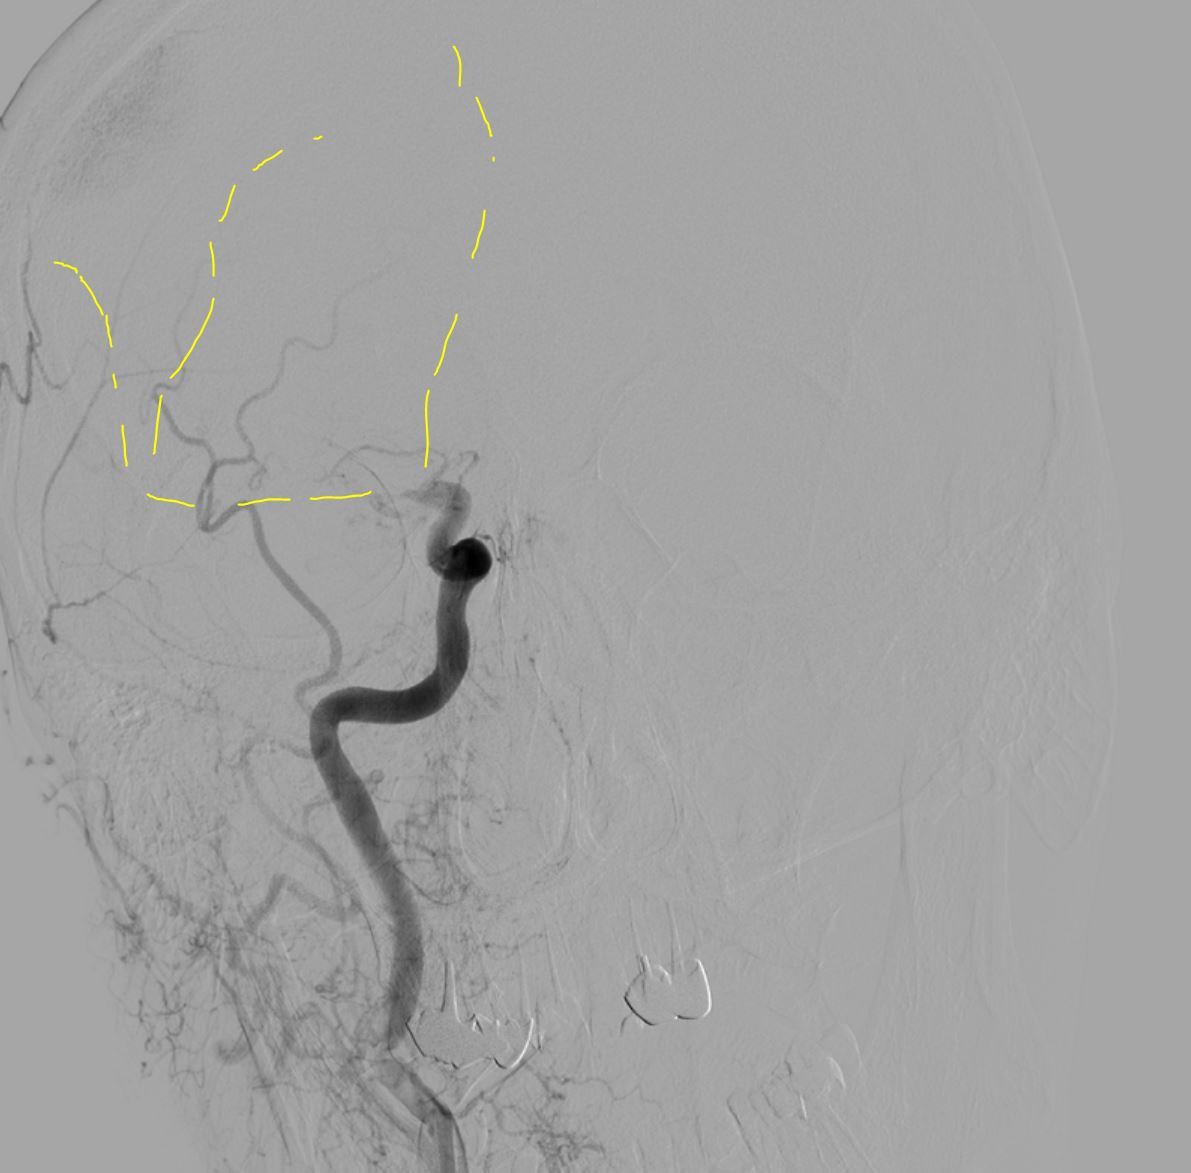

Делаю третью попытку...

Да уж... Но что то подсказывало, "еще разочек" )) Ок. давай еще попробуем...

Четвертая попытка.

Супер! Продолжаем...

В итоге после 5 попыток кровоснабжение правого полушария полностью восстановлено. Общее время операции около полутора часов, удалено много красных плотных тромбов. Дырку в ноге зашил Ангиосилом.

Результат ВСТЭ: оптимальный; Восстановление перфузии (mTICI) 3; Тип процедуры ЦАГ +ТА +ТЭ; Гемостаз AngioSeal 8F;